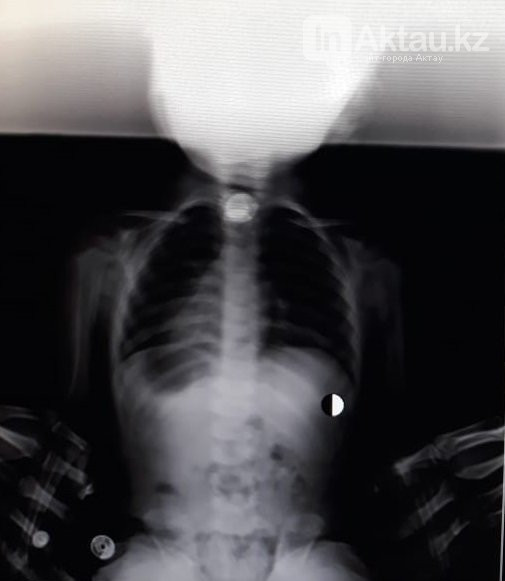

В Мангистауской области двухлетняя девочка едва не задохнулась, проглотив монету, сообщает Tengrinews.kz со ссылкой на ИнАктау.

Девочку с жалобами на затрудненное дыхание доставили в приемный покой Бейнеуской ЦРБ 18 марта. Сделав рентген, медики обнаружили в дыхательных путях ребенка инородный предмет.

По словам врачей, они решили не дожидаться отправки девочки в областную детскую больницу и попытались очистить дыхательные пути ребенка самостоятельно. "Врачи приняли решение вытаскивать инородный предмет, используя опыт испанских врачей, который, по словам директора Бейнеуской ЦРБ, он получил у заграничных коллег. Из дыхательных путей девочки врачи извлекли 10-тенговую монету. В настоящее время здоровью маленькой пациентки ничего не угрожает", -  рассказали в пресс-службе облздрава.